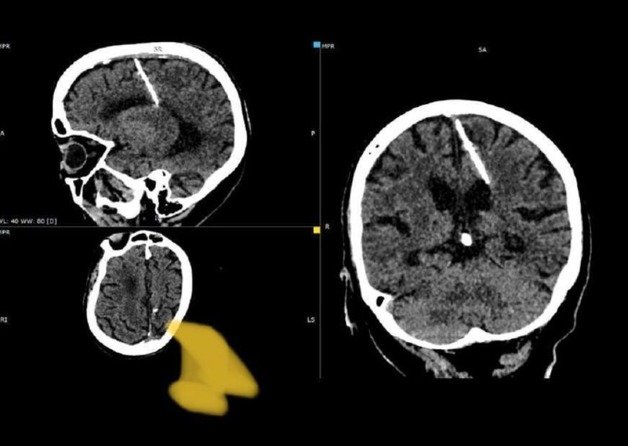

러시아의 80세 여성이 일평생 3㎝ 길이 바늘을 뇌에 꽂고 살아왔다는 사실이 알려지며 충격을 주고 있다.(텔레그램 갈무리).

러시아의 80세 여성이 일평생 3㎝ 길이 바늘을 뇌에 꽂고 살아왔다는 사실이 알려지며 충격을 주고 있다.

4일(현지시간) 러시아 사할린주(州) 보건부는 텔레그램을 통해 “지역 X선 전문의들은 80세 환자의 뇌에서 3㎝ 바늘을 발견했다”고 적었다.

이어 “바늘은 왼쪽에 들어갔지만, 예상된 결과를 초래하지는 않았다. 이 소녀는 살아남았다”며 “지금껏 그는 결코 두통을 앓지 않았다. 올해 컴퓨터 단층촬영에서 이물질이 검출됐을 뿐”이라고 덧붙였다.